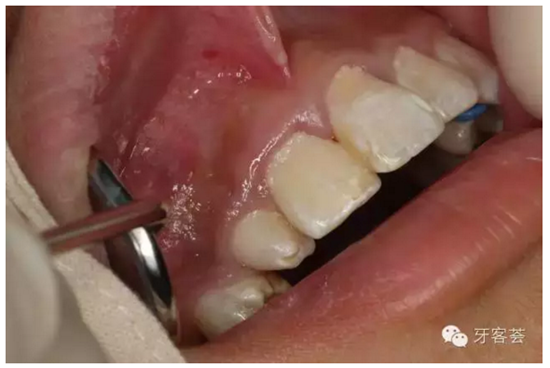

圖5:患者的口內(nèi)像:12位畸形牙,11牙冠顏色無異常、無松動。